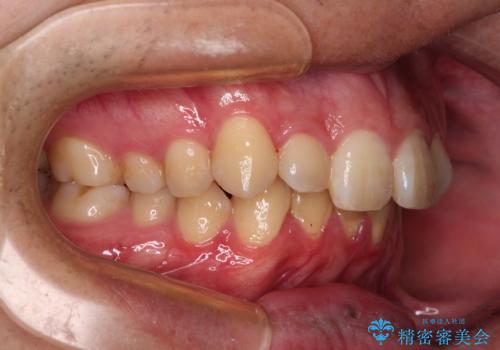

上下前歯にデコボコがありましたが、特に上顎の叢生が強く、通常に歯列を整えると、上顎が前方に突出し、口元の突出感が残った仕上がりとなる可能性が考えられました。

補助装置を用いて上顎歯列全体を後方に移動させる力をかけ、唇が閉じやすいような仕上がりを目指して、ワイヤー装置にて矯正治療を行うこととしました。

非常に咬合力が強く、左側の臼歯がなかなか後方へ移動できなかったのですが、2年ほどかけて大変満足のいく仕上がりを達成することができました。